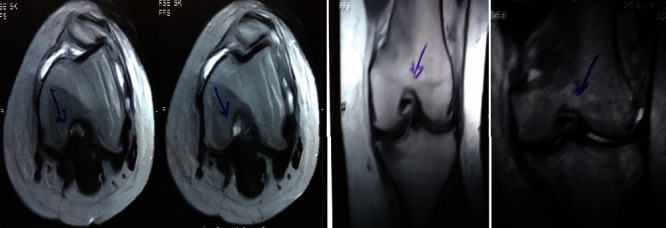

圖1:治療前MRI顯示內(nèi)側(cè)和外側(cè)半月板后角的III級(jí)撕裂。